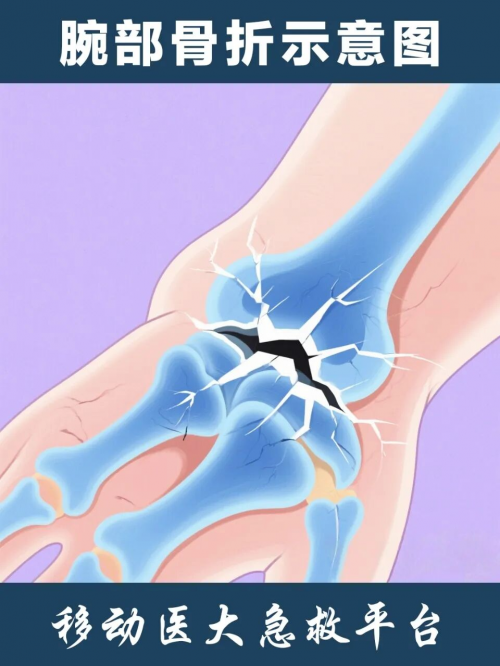

腕部骨折:老人跌倒时通常会本能地用手撑地,导致手腕部承受较大冲击力,易引发桡骨远端骨折,表现为腕部疼痛、肿胀、畸形,活动受限。